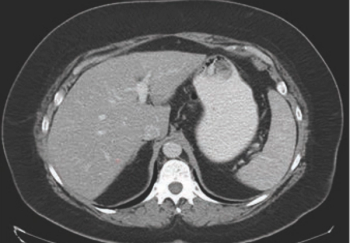

CT can provide faster, easier-to-capture evidence of non-alcoholic fatty liver disease than MRI or ultrasound elastography.